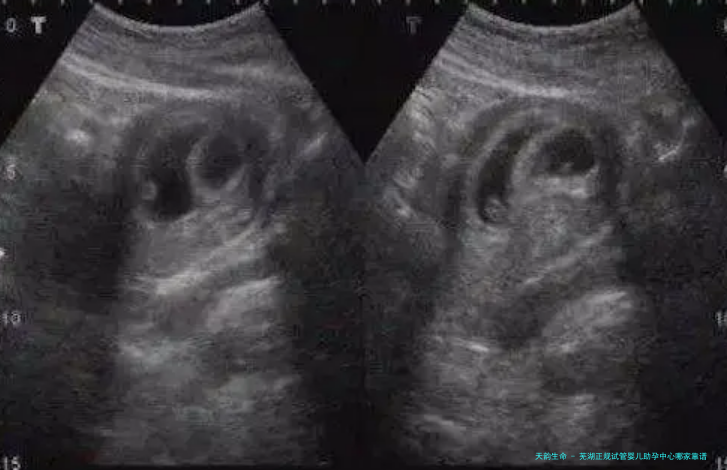

不同医院的试管婴儿成功率和费用存在必须的差别,主要取决于多种因素,如患者自身情况、医生的技术造诣以及实验室设备等。根据观察数据,芜湖市片面标准试管婴儿助孕中心的自愿卵子子子清新胚胎移植周期成功率在60%-75%之间,而治疗费在五万到十万元左右。